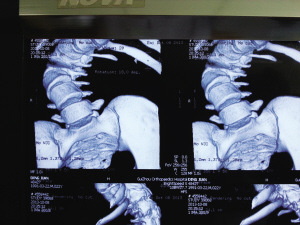

術前,小健脊柱側(cè)彎嚴重。

術后“長高”了12公分。

今年1月,小健感覺身體不適,便在親友陪同下來到省骨科醫(yī)院。經(jīng)檢查,醫(yī)生發(fā)現(xiàn)小健脊柱后凸彎近150度,側(cè)凸近130度,肺功能受損達30%。因小健已經(jīng)22歲,脊柱生長已經(jīng)停止,十分僵硬,錯過了最佳治療期,只能做脊柱側(cè)彎矯正手術,但該手術費用高,難度大。

8個小時的手術中,小健共被植入19根金屬釘。手術成功后,小健背部包塊不見了,身高從156公分“躥”到168公分。昨日,出院后的小健來到醫(yī)院復查,恢復結(jié)果良好。